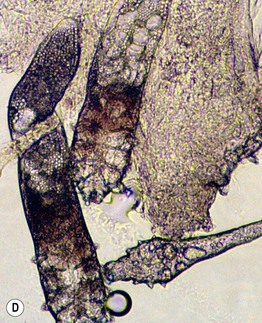

Fig. 31.4 Folliculitis – fungal, viral, and ectoparasitic. A Firm follicular papules of dermatophyte folliculitis (Majocchi's granuloma) in the setting of extensive tinea corporis. B Follicular herpes simplex viral infection in an immunocompromised host. C Edematous papules of Demodex folliculitis superimposed on the characteristic background erythema. D Microscopic findings of follicular contents obtained via scraping of Demodex folliculitis. B, Courtesy, Karynne O. Duncan, MD. C, Courtesy, Kalman Watsky, MD.